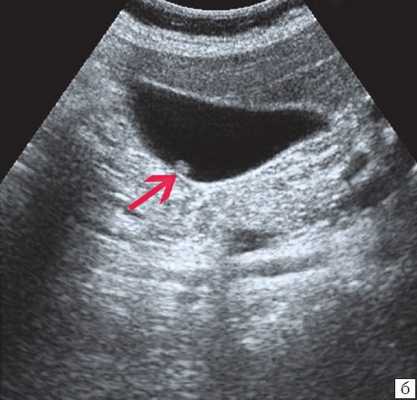

При низком билиарном блоке (обтурация на уровне холедоха, головки ПЖ, БДС) кроме расширенных внутрипеченочных протоков визуализируются расширенные внепеченочные протоки, желчный пузырь увеличен (рис. 2).

Рис. 1. Ультразвуковая картина билиарной гипертензии при механической желтухе.

а) Расширенные внутрипеченочные протоки.

б) Увеличенный желчный пузырь с густой взвесью (красная стрелка) и расширенный ОЖП (синяя стрелка).